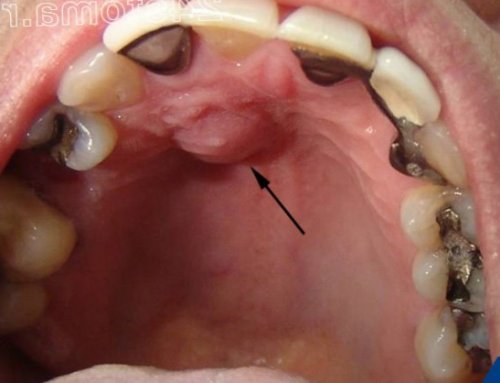

• ранее в проекции этого зуба на десне мог появляться свищ (рис.4),

• появлялась припухлость десны в проекции больного зуба (рис.5-6),